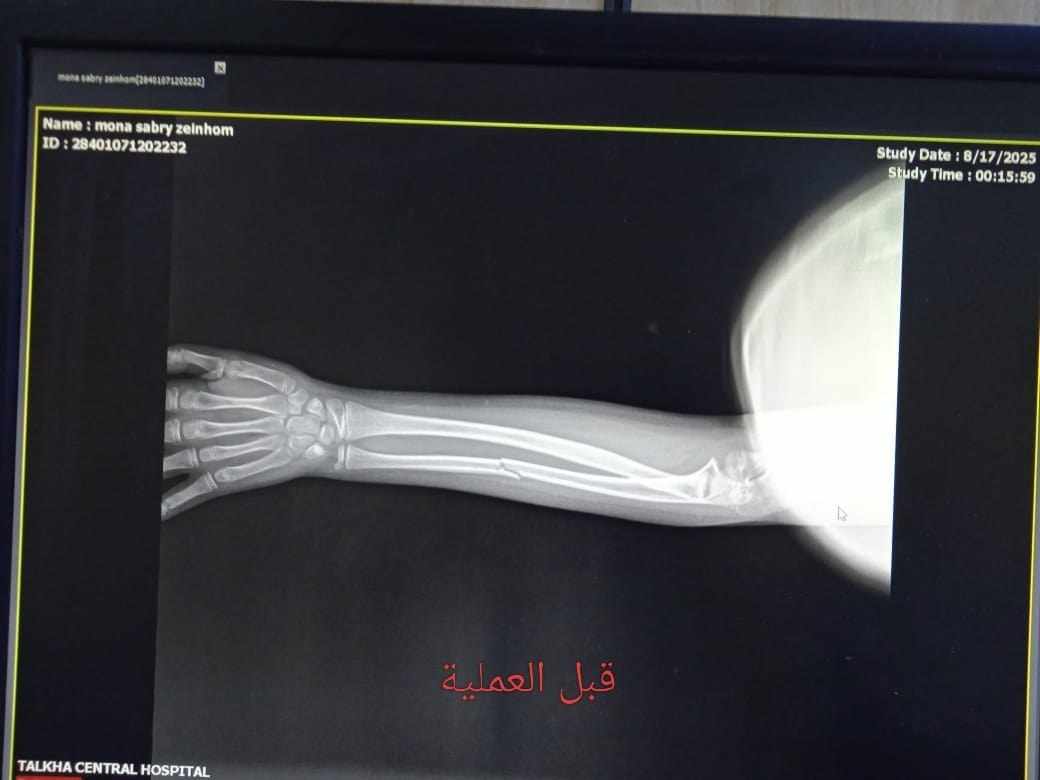

استقبلت مستشفى طلخا المركزي بمحافظة الدقهلية طفلة تعاني من كسر في عظمة الزند الأيسر، حيث جرى التعامل الفوري مع الحالة ونقلها إلى غرفة العمليات لإجراء التدخل الجراحي اللازم.

وذلك تنفيذًا لتعليمات الدكتور خالد عبد الغفار نائب رئيس الوزراء ووزير الصحة واللواء طارق مرزوق محافظ الدقهلية وبرعاية الدكتور حمودة الجزار، وكيل وزارة الصحة بالدقهلية، وإشراف مباشر من الدكتور السيد فاروق، وكيل المديرية للطب العلاجي،، والدكتورة لاميس حمدى، مدير مستشفى طلخا المركزي، حيث تم إجراء العملية بنجاح وتركيب مسمار نخاعي مرن بالزند الأيسر.